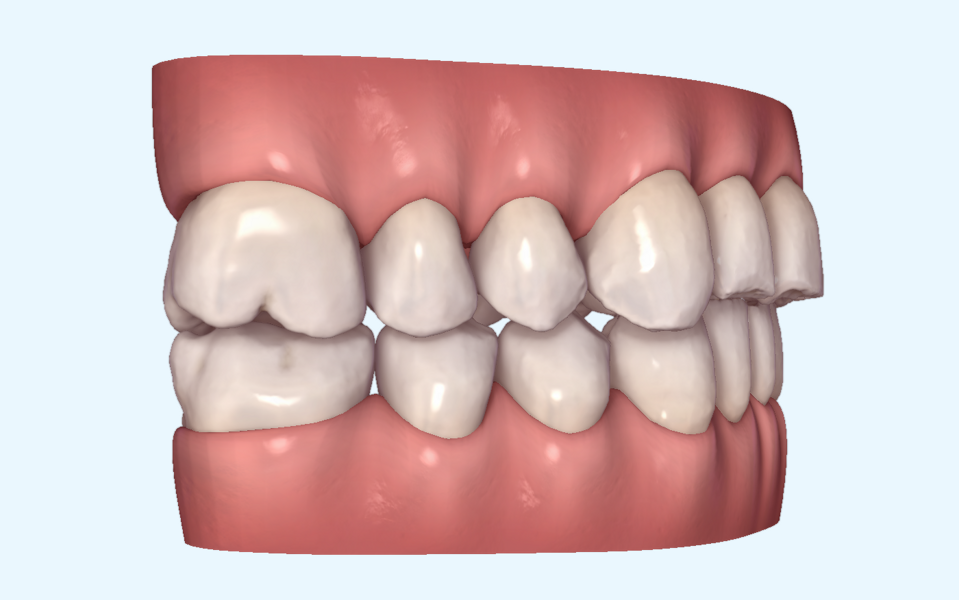

Tongue posture alteration, atypical swallowing and perioral muscle dysfunction from birth result in the development of jaw and dental dysmorphism. The masticatory muscles then reinforce functional alteration. Once altered during development, the oral cavity grows, matures and ages, progressively worsening the peculiar and groupable morphotypes (Figs. 1–5).

Static characteristics described by Mew are useful for classifying physiological and pathological morphology of development in children, as well as for anticipating or explaining altered evolution in adult patients (Fig. 6).15 Dynamic characteristics to be considered are the following:

Fig. 6: Mew classification based on tongue positioning.15